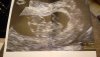

Kochane Dziewczyny!😊 ja tez po dzisiejszej wizycie jestem mega szczęśliwa - serduszko bije ❤️ Wszystko wygląda pięknie, 4mm szczęścia i wciąż rośnie!💛

z @ 7t 3d, a z USG 6t1d a przy moich długich cyklach - 35 i więcej dni jest to całkowicie w porzadku 😊

kolejna wizyta za 4 tygodnie, 26.10. Zobaczymy ile mały Agent podrośnie do tego czasu, oby zdrowo!☺️

09DE59C7-210B-4E44-967F-967C3859115A.jpeg